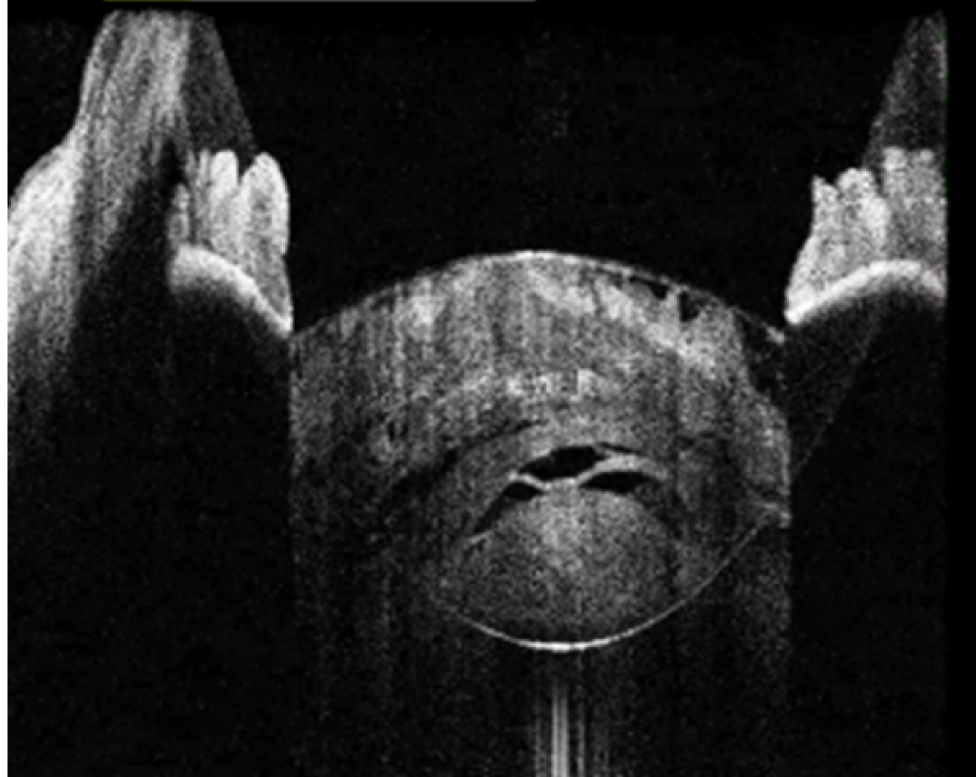

В исследование вошли 196 пациентов (250 глаз) с перезрелой катарактой. Пациенты были разделены на 2 группы (по 125 глаз в каждой группе). Всем пациентам интраоперационно с помощью интегрированной в операционный микроскоп И-ОКТ, Hi-R NEO (HAAG STREIT, Германия), определяли тип перезрелой катаракты (рис. 1–4).

Рис. 4. Тип 4 перезрелой катаракты: гомогенные передние кортикальные слои хрусталика вида «матового стекла»